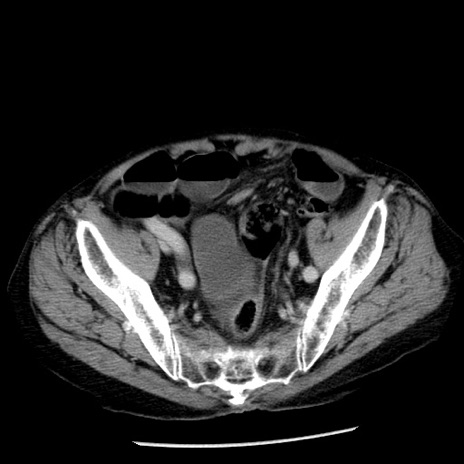

症例26(横断像)

【症例】80歳代男性

【主訴】嘔吐

【現病歴】昨晩2回嘔吐あり、今朝になっても嘔吐あり。来院。

【既往歴】胃潰瘍

【身体所見】意識清明、BT 37.6℃、BP 166/95mmHg、HR 100bpm、SpO2 97%、腹部:平坦・軟、腸蠕動音聴取良好、圧痛なし。

【データ】WBC 21900、CRP 1.46